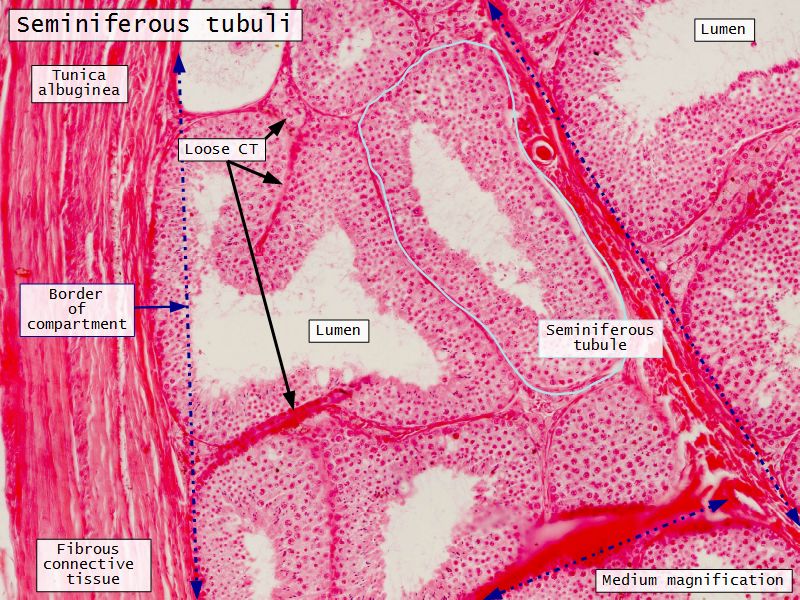

Tunica albuginea

- Thick fibrous CT capsule

- Forms septae

- Divide testis into lobuli

Lobuli

- Pyramidal shaped compartments

- Contain 1 - 4 seminiferous tubules each within

- Meshwork of loose CT

- AVN

- Leydig cells

Seminiferous tubuli

- Site of spermatozoa production

- 150 - 250 µm diameter